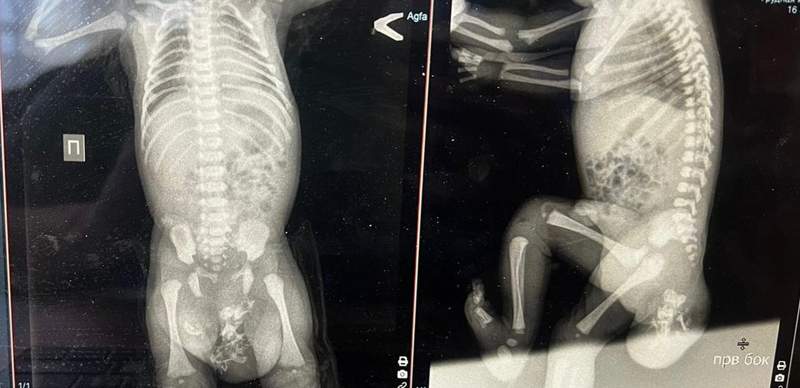

— Ребенок родился с пороком развития: крестцово-копчиковая тератома — разновидность опухоли, локализующейся в основании копчика. Это самая распространенная опухоль у детей периода новорожденности. Смешанная форма размером 10 на 8 сантиметров. На третьи сутки после рождения прооперировали, операция прошла успешно, образование полностью убрали, состояние ребенка удовлетворительное и он отправится домой, — говорит детский и неонатальный хирург, заведующий отделением гнойно-торакальной хирургии Саматбек Мырзахмет.